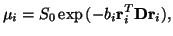

The diffusion tensor has often been used to model local diffusion

within a voxel (e.g. [10,15,16]). The

assumption made is that local diffusion may be characterized with a 3

Dimensional Gaussian distribution ([10]), whose covariance

matrix is proportional to the diffusion tensor,  . The

resulting diffusion weighted signal,

. The

resulting diffusion weighted signal,  along a gradient direction

along a gradient direction

, with

, with  -value

-value  is modeled as:

is modeled as:

where  is the signal with no diffusion gradients applied.

is the signal with no diffusion gradients applied.  ,